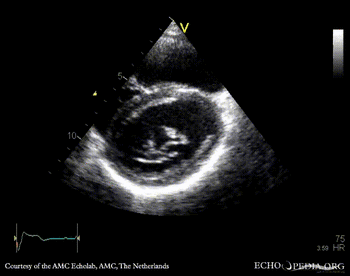

| PLAX: thickend mitral valve leaflets